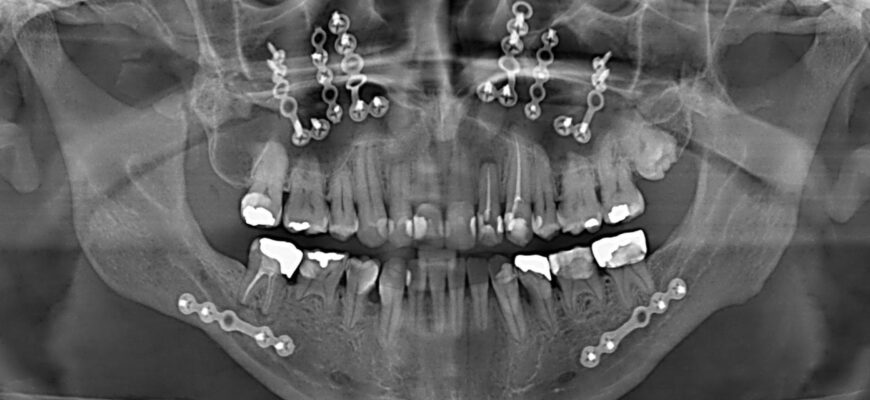

Процедура видалення кіст

Ви думаєте, просто пішов, видалив і все? А тут цілий процес: анестезія, вирізання, залікування. І це ще не все…

- Спочатку роблять місцеву анестезію. Нікому не хочеться відчувати біль.

- Потім – акуратна резекція кісти. Це, знаєте, таки мистецтво.

- І вже далі – шви, обробка, контроль болю.